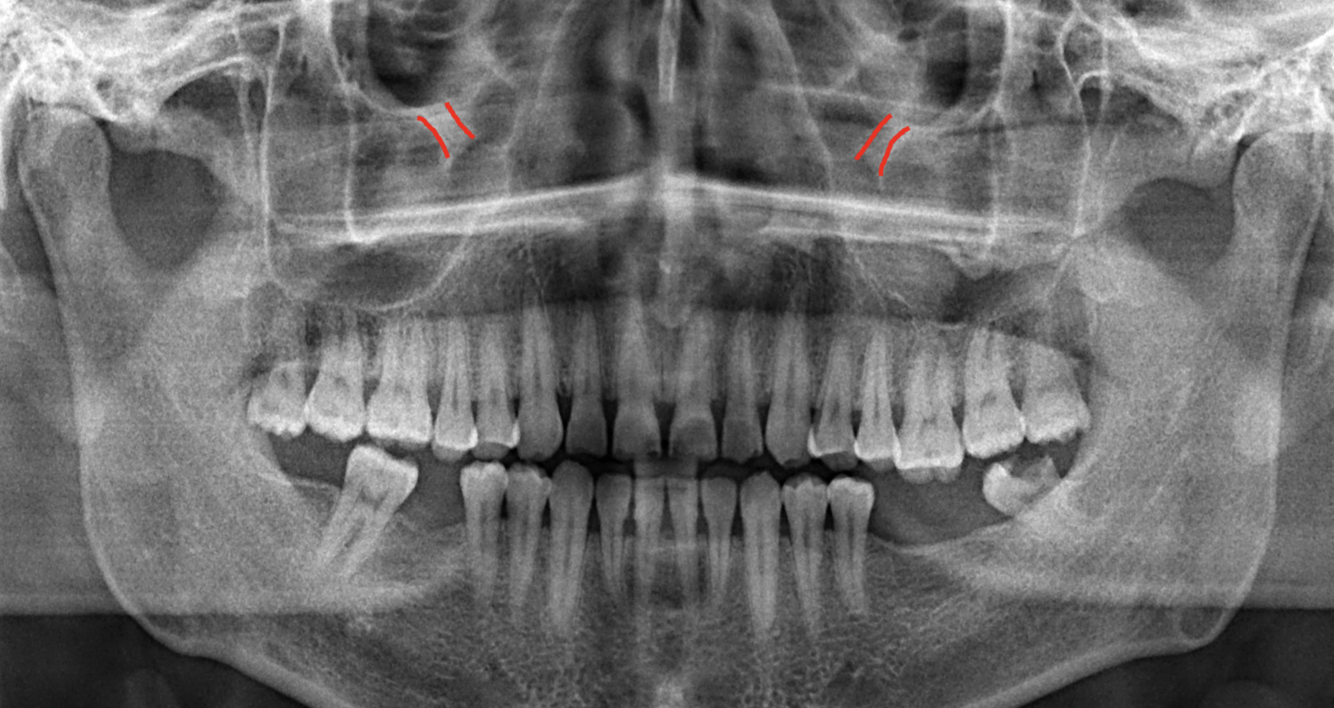

What does the red indicate in the following image?

A

Coronoid process